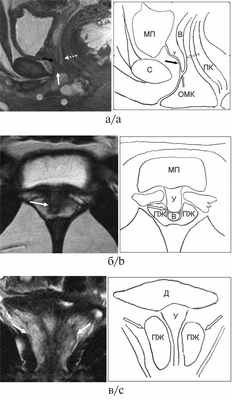

С целью определения объема и тактики оперативного лечения в обоих случаях проведено магнитно-резонансное томографическое (МРТ) исследование органов малого таза без контрастирования в режимах Т1, Т2, DW, выполненное на оборудовании Optima MR450w №415449 («GE Healthcare», США). В области уретры, проксимальнее уретровагинального конфлюенса выявлена ткань ПЖ, имеющая небольшой объем и отсутствие зональной дифференцировки. На МР-изображениях ткань ПЖ располагается типично для мужской ПЖ в парауретральной области, за лобковым симфизом, книзу от мочевого пузыря, эллипсоидной формы, представлена преимущественно железистой тканью периферической зоны, однородной структуры с гиперинтенсивным гомогенным сигналом в режиме Т2-ВИ и изоинтенсивным сигналом в режиме Т1-ВИ (рис. 1, 2). Комплексное уродинамическое исследование (КУДИ) не выявило признаков инфравезикальной обструкции (см. табл. 2). При цистоуретровагиноскопии, проведенной непосредственно перед операцией, выявлены высокий уретровагинальный конфлюенс и признаки гранулярного цистита в области треугольника Льетто у обеих девочек. Особенностью патологического строения мочеполовых путей у пациентки 2 явилось резкое сужение входа во влагалище. Последний открывался отверстием диаметром 0,3 см, окруженным складкой слизистой (гименальным кольцом) над уровнем тазовой диафрагмы. Показания к проведению второго этапа феминизации у пациентки 1 обоснованы в связи с наступлением первой менструации и достаточной эстрогенизацией гениталий [3]. Пациентка 2 не достигла менархе. С учетом эндоскопической находки в виде резкого сужения входа во влагалище и риска развития клиники гематокольпос и гематометра при наступлении менархе в будущем вследствие нарушения оттока менструальных выделений принято решение о проведении второго этапа феминизации. Пациенткам проведена разобщающая мочевые и половые пути интроитопластика. Выполнена полная мобилизация общего мочеполового канала (ОМК) с формированием передней стенки искусственного входа во влагалище (ИВВ) слизистым лоскутом в модификации Passorini—Glasel. Задняя стенка ИВВ сформирована с помощью омега-образного кожного лоскута промежности. Неоуретра и неомеатус сформированы из участка ОМК. Пациентки выписаны из стационара в удовлетворительном состоянии на 9-е и 11-е сутки после операции. Рекомендовано следующее: гормональная терапия, получаемая пациентками на момент поступления (см. табл. 2); ежеквартальный контроль уровней 17-ОНП, тестостерона, АКТГ и ренина плазмы крови для оценки компенсации глюкокортикоидной и минералокортикоидной недостаточности; наблюдение гинеколога; контрольная МРТ малого таза; уродинамическое исследование через 6—12 мес для оценки результата операции и динамики роста ПЖ; ежегодный контроль уровня простатического специфического антигена (ПСА) и повторная МРТ в случае его увеличения.

Рис. 1. Серия МРТ малого таза в режиме Т2-ВИ со скицами пациентки 1, 17 лет, с диагнозом «ВДКН, сольтеряющая форма».

а — сагиттальная плоскость; б — аксиальная плоскость; в — фронтальная плоскость. На изображениях визуализируются уретра (черная стрелка), влагалище (белая пунктирная стрелка) с наличием в просвете небольшого количества жидкости. Уретровагинальный конфлюенс (белая стрелка) определяется на уровне средней трети симфиза. Круглыми МРТ метками на рис. а обозначены наружное отверстие общего мочеполового канала, расположенное ближе к симфизу, и проекция входа во влагалище, расположенного ближе к прямой кишке. Визуализируется ткань предстательной железы (головки черных стрелок), эллипсоидной формы, без четкой зональной дифференцировки, размерами 34×15×32 мм (объем 8,4 см 3 ) без видимых очаговых изменений в структуре. МП — мочевой пузырь, С — симфиз, У — уретра, В — влагалище, ОМК — общий мочеполовой канал, ПК — прямая кишка, ПЖ — предстательная железа, Д — детрузор мочевого пузыря.

Рис. 2. Серия МРТ малого таза со скицами пациентки 2, 16 лет, с диагнозом «ВДКН, сольтеряющая форма».

а — корональная плоскость в режиме Т2-ВИ; б — аксиальная плоскость в режиме Т2-ВИ с подавлением сигнала от жировой ткани. Визуализируется ткань предстательной железы (белые головки стрелок), эллипсоидной формы, без четкой зональной дифференцировки, размерами 30×14×21 мм (объем 4,6 см 3 ). Структура предстательной железы представлена преимущественно железистой тканью периферической зоны, однородной структуры с гиперинтенсивным гомогенным сигналом без видимых очаговых изменений. МП — мочевой пузырь, С — симфиз, У — уретра, В — влагалище, ПК — прямая кишка, ПЖ — предстательная железа.